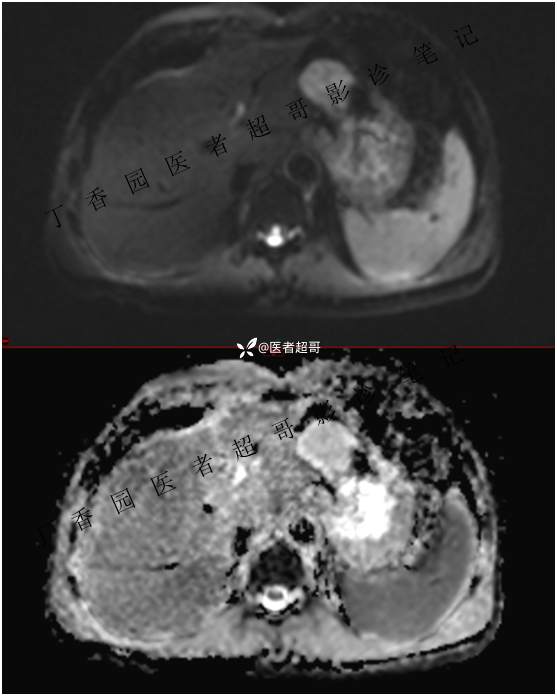

肝胃间隙肿瘤,间质瘤?平滑肌瘤?还是鞘瘤?有结果,请分析!

现病史:患者于3天前查体行肝胆脾胰肾彩超示肝内实性占位,无恶心、呕吐,无发热、寒战,无腹胀、腹泻,进一步于医院行上腹部CT增强示:肝胃交界处肿块。未行特殊治疗。今患者为求进一步治疗,来我院就诊,门诊以“肝占位性病变”收入院。患者自发病以来,神志清,精神可,饮食睡眠可,二便可,体重近期未见明显变化。